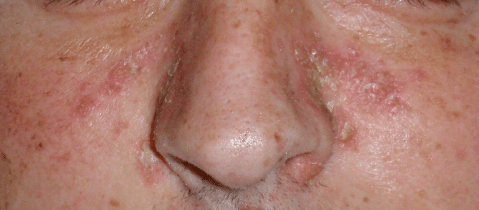

ROZASEA

Gül hastalığı ya da rozasea , oldukça sık görülen bir deri hastalığıdır. Güneş, stres ve birtakım yiyeceklerin tetiklediği bu hastalıkta cilt kızarır, yangılanır ve kızarıklık yayılır. Rozasea’nın ciddiyeti kişiden kişiye değişir. Hastalığın nedeni kesin olarak bilinmemektedir. En önemli belirtilerinin başında yüzün orta kısımlarında meydana gelen kızarıklıklar gelir. Özellikle burun etrafındaki ve elmacık kemiklerinin üzerindeki bölgelerde bulunan kılcal damarlarda şişmeler ve kızarmalar olur. Diğer bir belirtisi ise, sivilcelerdir. Burunda kabarcıklar da meydana gelebilir. Rozasea her yaşta görülebilen bir deri hastalığıdır. Kadınlarda daha çok görülür. Gül hastalığı bulunan kişiler baharatlı ve kafeinli yiyecek-içeceklerden uzak durmalıdır. Güneş ışığına fazla maruz kalmamalı ve güneş kremi kullanmalıdır.

CloseROZASEA

Gül hastalığı ya da rozasea , oldukça sık görülen bir deri hastalığıdır. Güneş, stres ve birtakım yiyeceklerin tetiklediği bu hastalıkta cilt kızarır, yangılanır ve kızarıklık yayılır. Rozasea’nın ciddiyeti kişiden kişiye değişir. Hastalığın nedeni kesin olarak bilinmemektedir. En önemli belirtilerinin başında yüzün orta kısımlarında meydana gelen kızarıklıklar gelir. Özellikle burun etrafındaki ve elmacık kemiklerinin üzerindeki bölgelerde bulunan kılcal damarlarda şişmeler ve kızarmalar olur. Diğer bir belirtisi ise, sivilcelerdir. Burunda kabarcıklar da meydana gelebilir. Rozasea her yaşta görülebilen bir deri hastalığıdır. Kadınlarda daha çok görülür. Gül hastalığı bulunan kişiler baharatlı ve kafeinli yiyecek-içeceklerden uzak durmalıdır. Güneş ışığına fazla maruz kalmamalı ve güneş kremi kullanmalıdır.